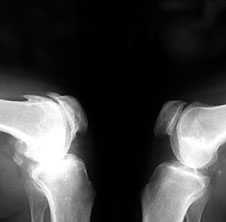

Рис. 2. Rо-графия коленных суставов в боковой проекции.

Артроз феморопателлярных суставов (больше слева). Артроз коленных суставов (I ст по Kollgren справа, IV ст. по Kollgren слева)